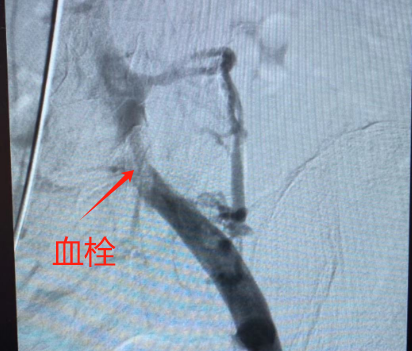

微创外一科团队医生与患者及家属充分沟通,立即行下腔静脉滤器置入术+左侧髂总静脉血栓抽吸取栓术+左侧髂总静脉狭窄球囊扩张术+左侧髂总静脉支架置入术。术后下肢肿痛缓解,患者当天下床活动,3天后顺利出院。